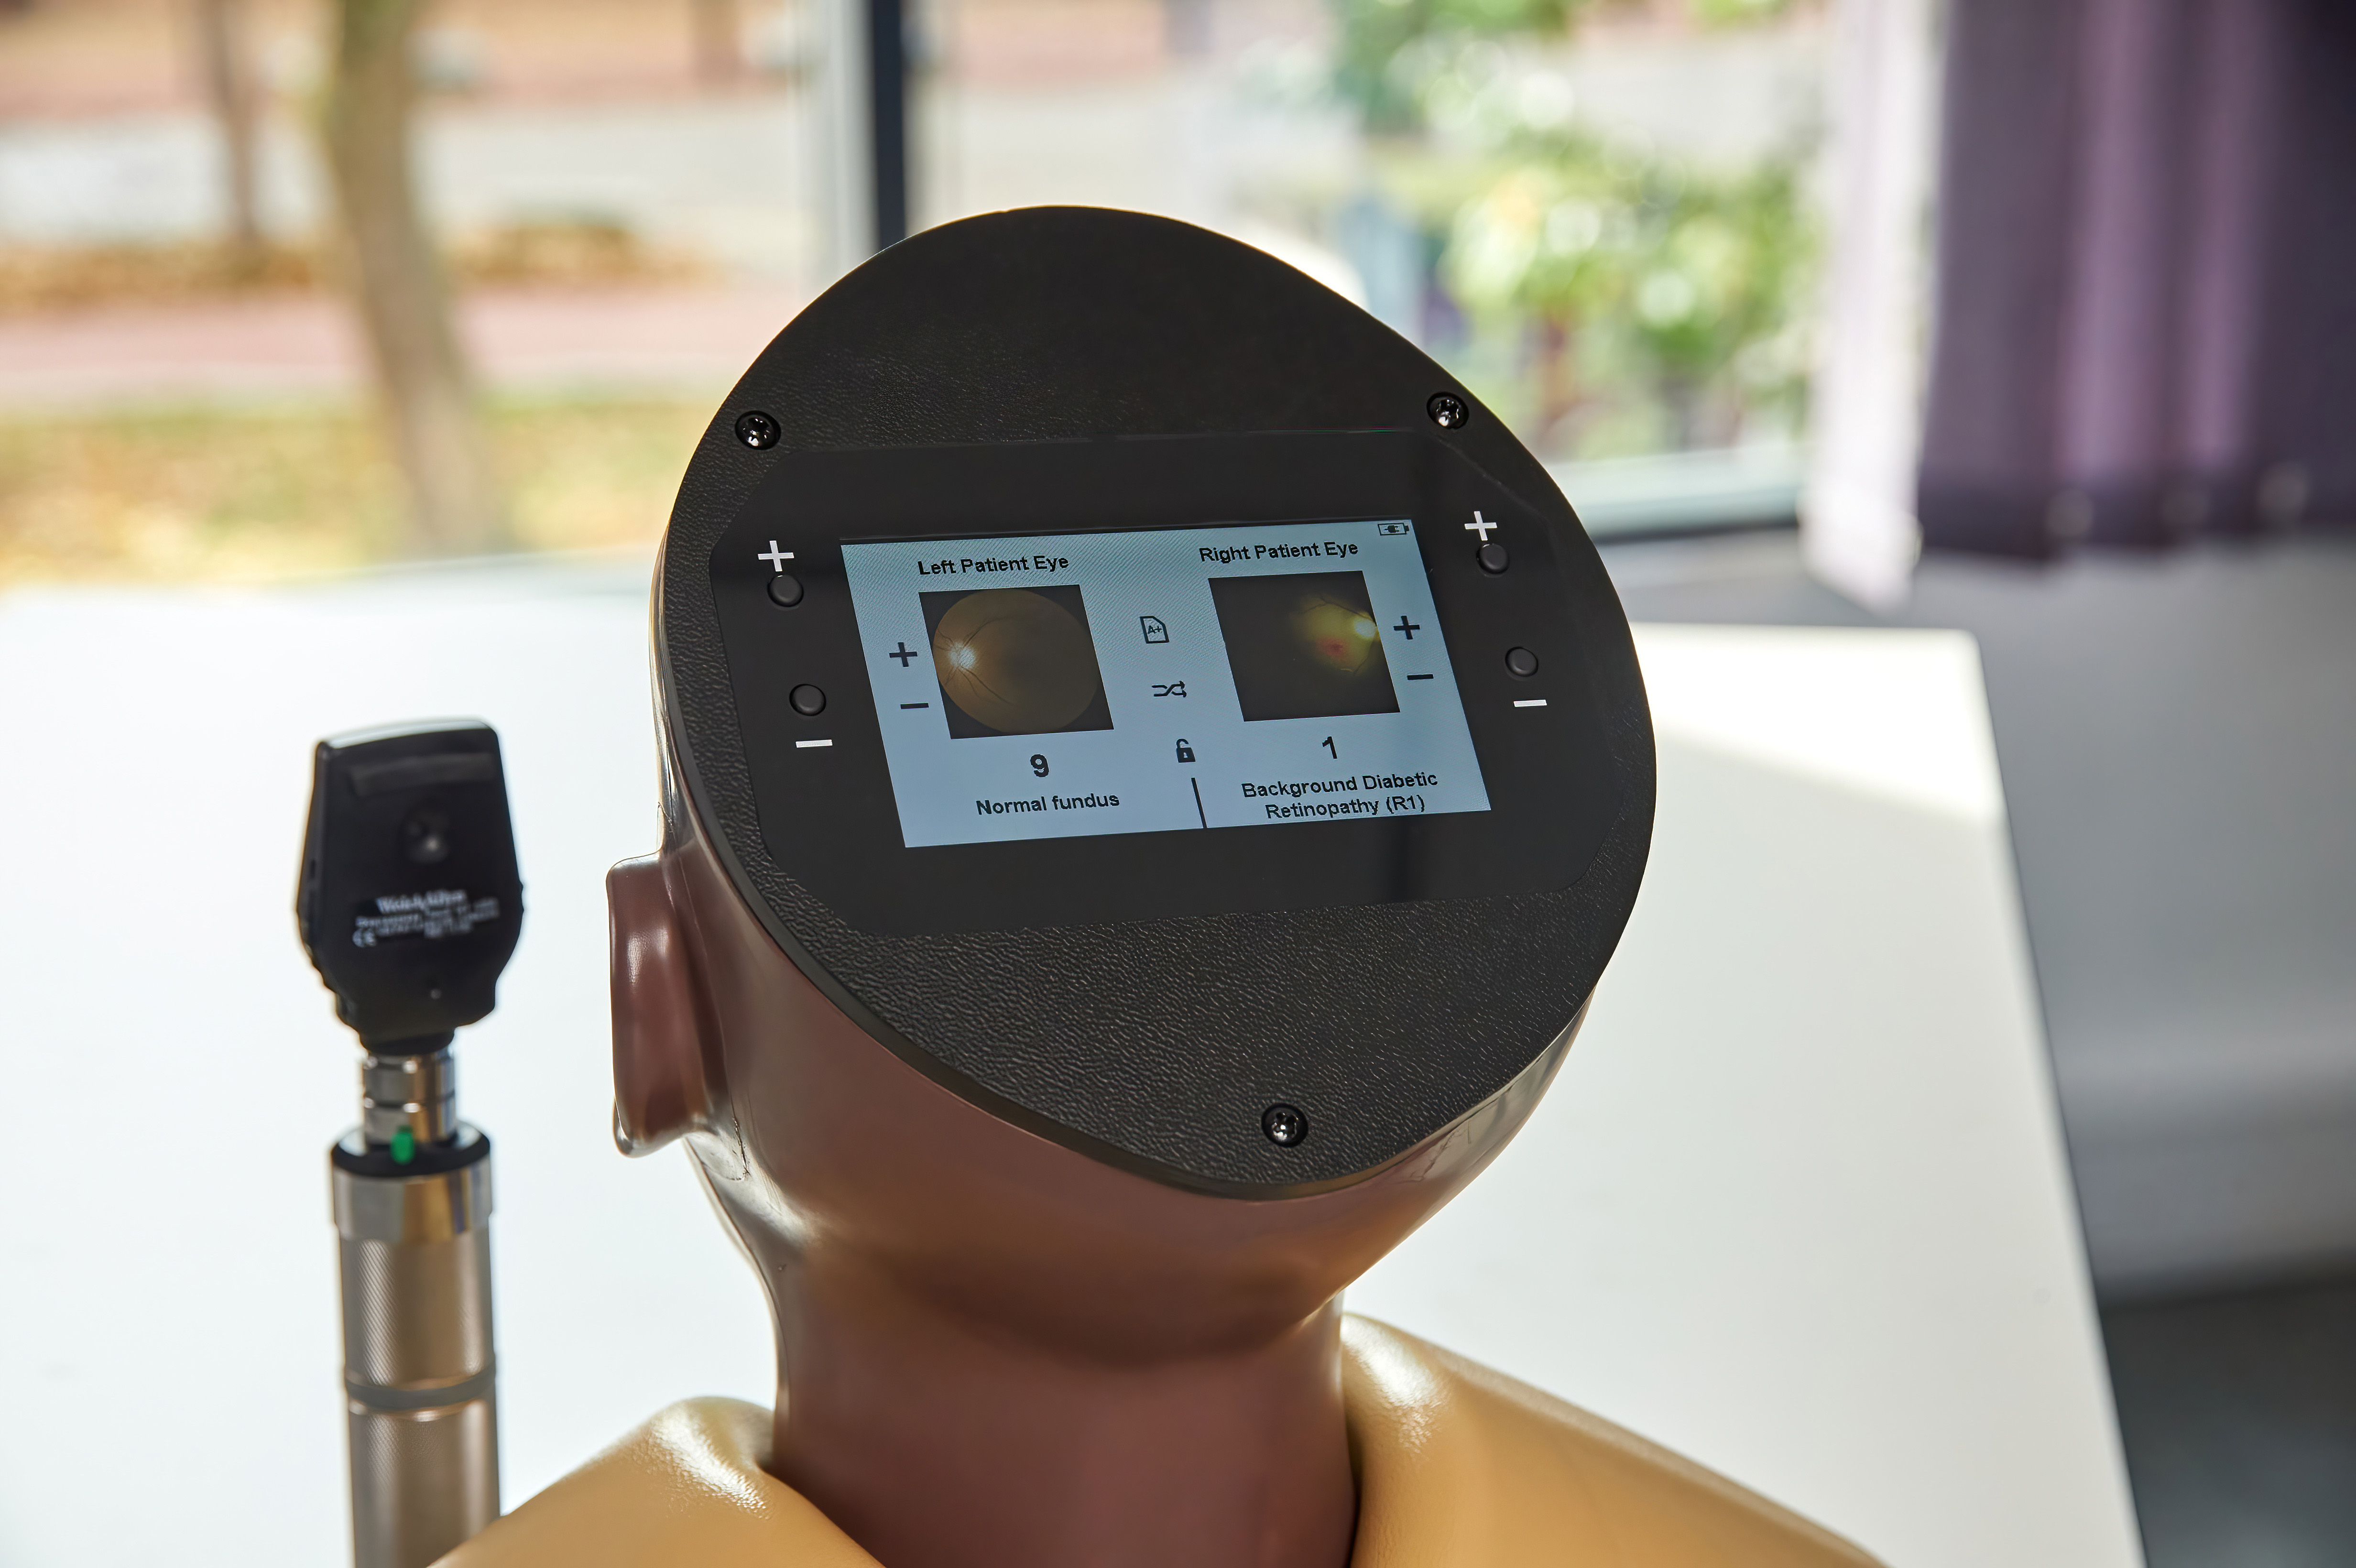

Inside the model, conditions are displayed with greater clarity and true-to-life colour on high-resolution circular LCD screens. A 4.3-inch external touchscreen interface makes operation intuitive and effective, allowing users to preview, search, and select conditions or build customisable sets for teaching, self-directed learning, or examination scenarios.

Condition Library: browse names and image previews for all 36 eye conditions

Search Function: instantly locate a condition for teaching or self-directed study

Random Mode: display conditions in a varied sequence to keep learners interested

Custom Sets: select up to 10 specific conditions in any order, for focused teaching or assessments

Exam Mode: hide condition names and numbers for authentic test conditions. Sleep Mode is automatically disabled for uninterrupted practice

Lock Mode – displays the last selected condition for both left and right patient eyes

Digital Eye Conditions

Eye conditions and diseases presented digitally for the light skin toned patients AR503 and dark skin toned patients AR503/50:

Diabetic Retinopathy:

Background Diabetic Retinopathy (R1) with Maculopathy (M0)